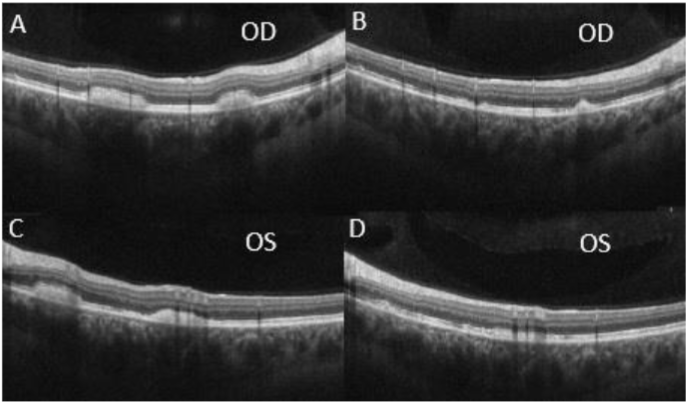

FAF revealed an increased number of hyper-autofluorescent flecks along the arcades and within the posterior pole.

At this time, the differential diagnosis included autosomal recessive Bestrophinopathy, BVMD, Juvenile X-linked Retinoschisis (JXLR or XLRS), toxic retinopathy, as well as paraneoplastic polymorphous retinopathy due to the patient’s significant tobacco history. Further diagnostic work-up was deemed necessary at this time to determine the etiology of this patient’s presentation and the patient was subsequently referred for genetic testing, electroretinogram (ERG)/electrooculogram (EOG), and a paraneoplastic etiology work-up. The patient’s genetic testing for the BEST1 gene returned negative and the patient’s ERG/EOG resulted in a borderline EOG result with normal Arden ratio in the right eye (1.85) and reduced Arden ratio in the left eye (1.51). The paraneoplastic evaluation was notable for a computerized tomography scan which showed a 1cm hilar lymphadenopathy and a subsequent endobronchial ultrasound biopsy was noted to have a benign-appearing morphology with low-risk for malignancy. During this time, interval OCT scans showed improvements with resolution of subretinal fluid at 11 months and reduction of the vitelliform lesions in the peripheral macula from 15 to 17 months at initial presentation.

In terms of other tools that an ophthalmologist could use to help narrow the differential diagnoses, diagnostic imaging remains an important means of differentiating between different retinal disorders. Fundus autofluorescence (FAF) is a non-invasive diagnostic imaging tool that utilizes lipofuscin to highlight areas in the RPE where there is pathology. Given that the development of AEPVM is marked by lipofuscin overaccumulation, the intensity of the vitelliform lesions in FAF is directly correlated with the amount of lipofuscin. Ocular Coherence Tomography (OCT) is another non-invasive diagnostic imaging test that can show serous detachment, as well as other pathology, present in the macula. This modality can be used to show the extent of the serous detachment and be used to track its improvement or worsening over time. Although these can be used in many other ocular conditions, the utilization of these diagnostic imaging studies can be extremely useful in narrowing the differential diagnoses and determining the degree of the disease when regarding AEPVM.